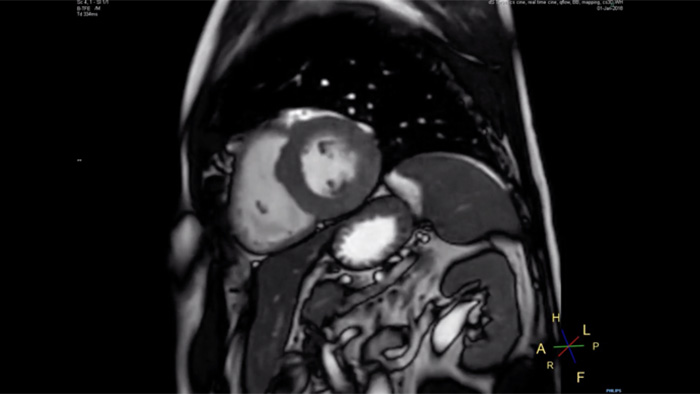

Up to 40% reduction in breathholds, with virtually equal image quality1

Philips Compressed SENSE reduces the time spent in the MRI scanner for the patient. Furthermore, Compressed SENSE enables the reduction of breath hold times which has the potential to improve compliance with an MRI scan.

4.8 sec breath hold time

Since short breath hold times make it easier for our patients to comply, the failure of breath holding largely disappeared.

At our facility, we found in Cardiac MR fewer breath holds are now needed, or breath hold times are shortened."

Dr. Takashi Koyama, MD, PhD, Diagnostic Radiologist and Director of the Department of Radiology Center and Diagnostic Radiology, Kurashiki Central Hospital, Japan

A 15- or 16-second breath-hold is tough for many cardiac patients. With Compressed SENSE we actually have protocols now that can get that below 10 seconds. It’s a lot easier to get through for a patient, and patients are a lot more satisfied with the experience.”

Trevor Andrews, Ph.D., MR Physicist, University of Vermont Medical Center, USA

Short breath holds, enhanced image quality and scan time

Compare the breath hold time of an MRI scan performed with Compressed SENSE MRI software versus a conventional scanning technique

12 sec breath hold